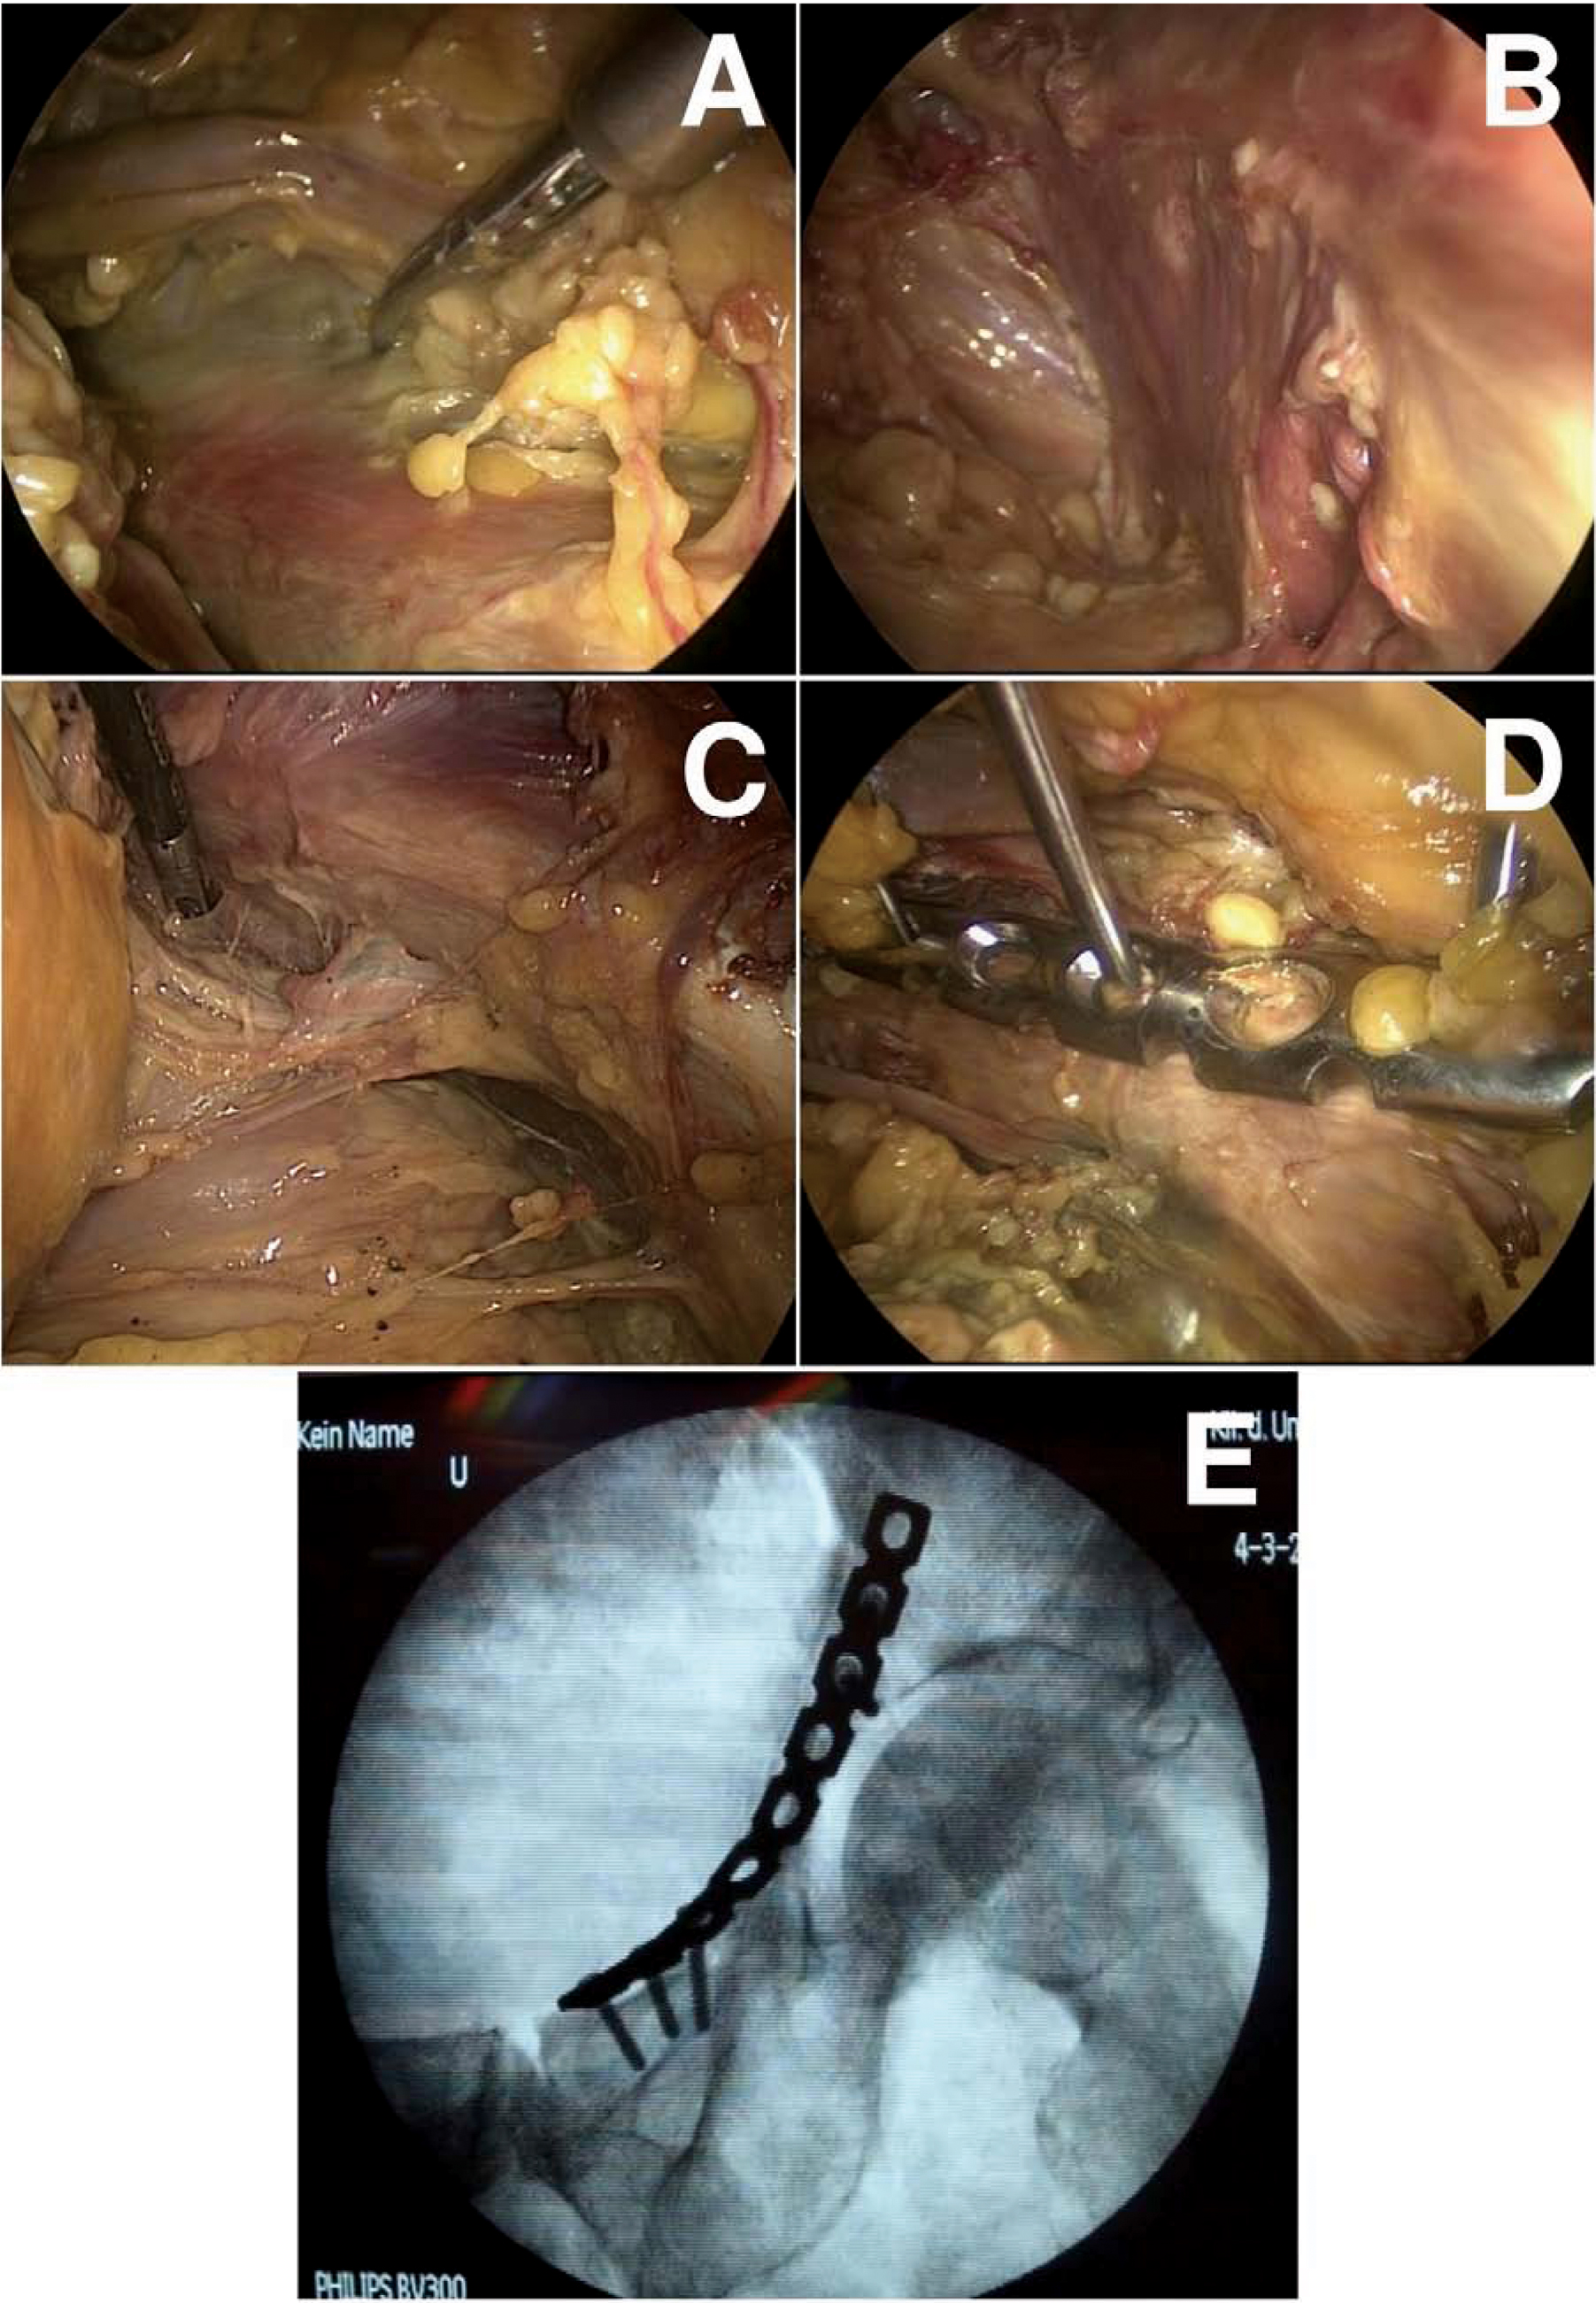

In 4 human cadavers, who donated themselves for scientific and educational purposes, we established the completely endoscopic preparation and visualization of all relevant structures of the complete pelvic ring from the symphysis to the iliosacral joint including the quadrilateral face and the greater sciatic notch with the sciatic nerve. Then, a plate osteosynthesis of the acetabulum along the iliopectineal line was done with standard laparoscopic instruments.

The visualization of the relevant anatomical structures for surgery of the acetabulum (iliac and femoral vessels, femoral nerve, obturator vessels, quadrilateral face, pelvic brim with the iliopectineal line until the iliosacral joint and the greater sciatic notch with the sciatic nerve; Fig A-C) as well as the completely endoscopic plate osteosynthesis along the iliopectineal line (Fig. D+E) can be done with standard laparoscopic instruments using 3 up to 10mm wide skin incisions.

The endoscopic visualization of the relevant anatomical structures is well possible. The plate osteosynthesis of the acetabulum itself requires an extracorporal forming of the plate using an anatomical specimen. The creation of such a specimen could be done using 3D-printing of 3D-data acquired out of CT-scans. Before introducing this endoscopic technique into a clinical setting, the question of reducing acetabular fractures is under investigation in anatomical and biomechanic studies.